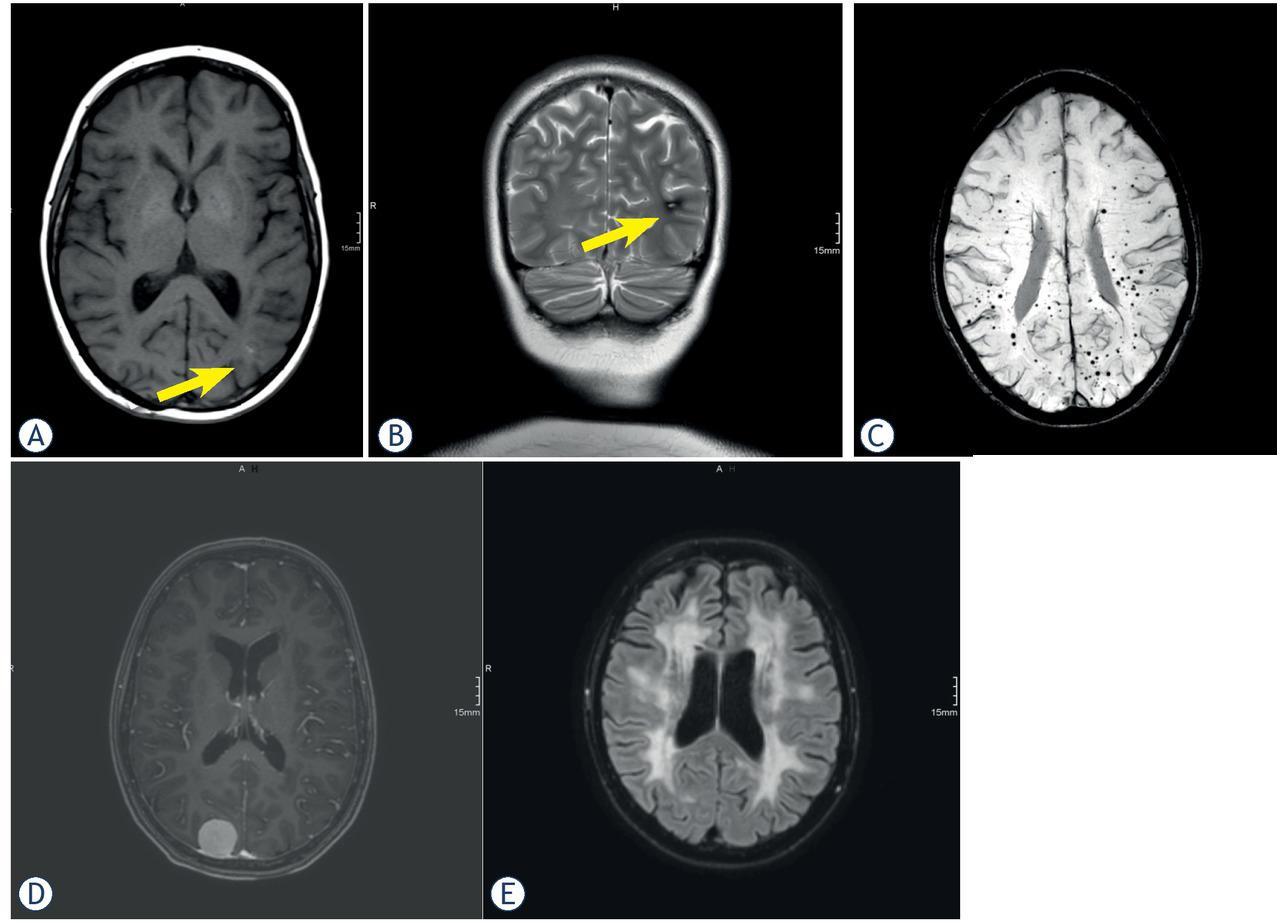

Examples of radiation-induced cavernomas with a type II lesion (A, B) and multiple type IV lesions (C) according to the Zabramski classification. Radiation-induced meningioma (D) and leukoencephalopathy with brain atrophy (E).

All 9 childhood cancer survivors with treated medulloblastoma developed RIC (100%). Occurrences of RIC dependent on the other tumor entities were: ALL 3/13 (23%), AML 3/5 (60%), pilocytic astrocytoma 1/2 (50%), germinoma 1/3 (33%) and ependymoma 1/3 (33%). One patient with craniopharyngeoma did not develop RIC. We classified RIC only in 1 patient (3%) with ALL (Zabramski type II) and in 2 patients (6%) with medulloblastoma (Zabramski type I and type II) as high risk for hemorrhage while all other detected RIC were classified as Zabramski type IV with low risk for hemorrhage. We did not find any statistically significant difference between RCI with low and high risk for hemorrhage depending on the original tumor entity (p = 0.737). We did not categorize RIC as Zabramski type III or V, in accordance with the proposal of Nikoubashman et al.14 Thus, only 3/18 childhood cancer survivors with RIC (17%) and 3 (8%) of all reviewed childhood cancer survivors with at least 2 brain MRI examinations developed lesions with a high risk for hemorrhage. As a main result of the study none of the childhood cancer survivors with RIC showed symptomatic intracranial hemorrhages. The localization of RIC was only supratentorial in 15 of the 36 childhood cancer survivors (42%), in two childhood cancer survivors only infratentorial (5%) and in 19 childhood cancer survivors both supra- and infratentorial (53%). RIC occurred after cranial radiotherapy in a median time period of 15.5 years (IQR 5–27). Six of the 36 childhood cancer survivors (17%) showed dynamic findings of RIC, and there were changes in the number and/or size of individual RIC without any accompanying changes in the Zabramski classification. Three childhood cancer survivors (8%) developed only a single RIC documented in brain MRI. Table 3 shows the summarized results. Examples of brain magnetic resonance imaging from childhood cancer survivors during long long-term follow-up are shown in Figure 2.